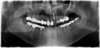

vue panoramique du cas précédent, avec extraction- implantation immédiate d’un implant avec pose d’un pilier et d’une couronne provisoires, au niveau de l’incisive latérale supérieure gauche

vue panoramique avec extraction- implantation immédiate d’un implant avec pose d’un pilier et d’une couronne provisoires, au niveau de l’incisive latérale supérieure droite

vue panoramique avec extraction- implantation immédiate de 2 implants avec pose de 2 piliers et de 2 couronnes provisoires, au niveau des 2 incisives centrales supérieure.